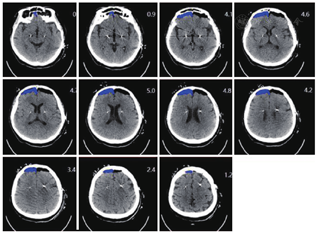

所有入组病例均于术后2 h和术后1周复查头部三维重建,将术后CT图像传输至ROSA计算机工作站中,并与术前CT融合,在"Axial(AC-PC)"图像上选取靶点平面,计算植入电极中心位置与手术计划相对应靶点在X轴和Y轴上的偏差距离。ICA体积由术后2 h复查CT逐层测量相加得出(图1,图2,图3)。

分别记录两侧电极X轴、Y轴在术后2 h及术后1周与术前计划融合误差的差值,在术后2 h复查CT中算出1CA的体积,其中104例患者第一侧电极发生1CA。第一侧植入电极X轴的误差变化△X1(0~1.15)mm,平均(0.13±0.18)mm,对应1CA体积(0.1~39.3)cm3,平均(6.95±7.35)cm3,差异无统计学意义(r=0.038,P>0.05);Y轴的误差变化△Y1(0~1.18)mm,平均(0.22±0.25)mm,差异有统计学意义(r=0.352,P<0.05),图4,图5。

第二侧电极中113例患者发生1CA,第二侧植入电极X轴的误差变化△X2(0~1.19)mm,平均(0.16±0.19)mm,对应1CA体积(0.05~38.2)cm3,平均(5.97±7.24)cm3,差异无统计学意义(r=0.009,P>0.05);Y轴的误差变化△Y2(0~1.4)mm,平均(0.23±0.21)mm,差异有统计学意义(r=0.513,P<0.05),图6,图7。